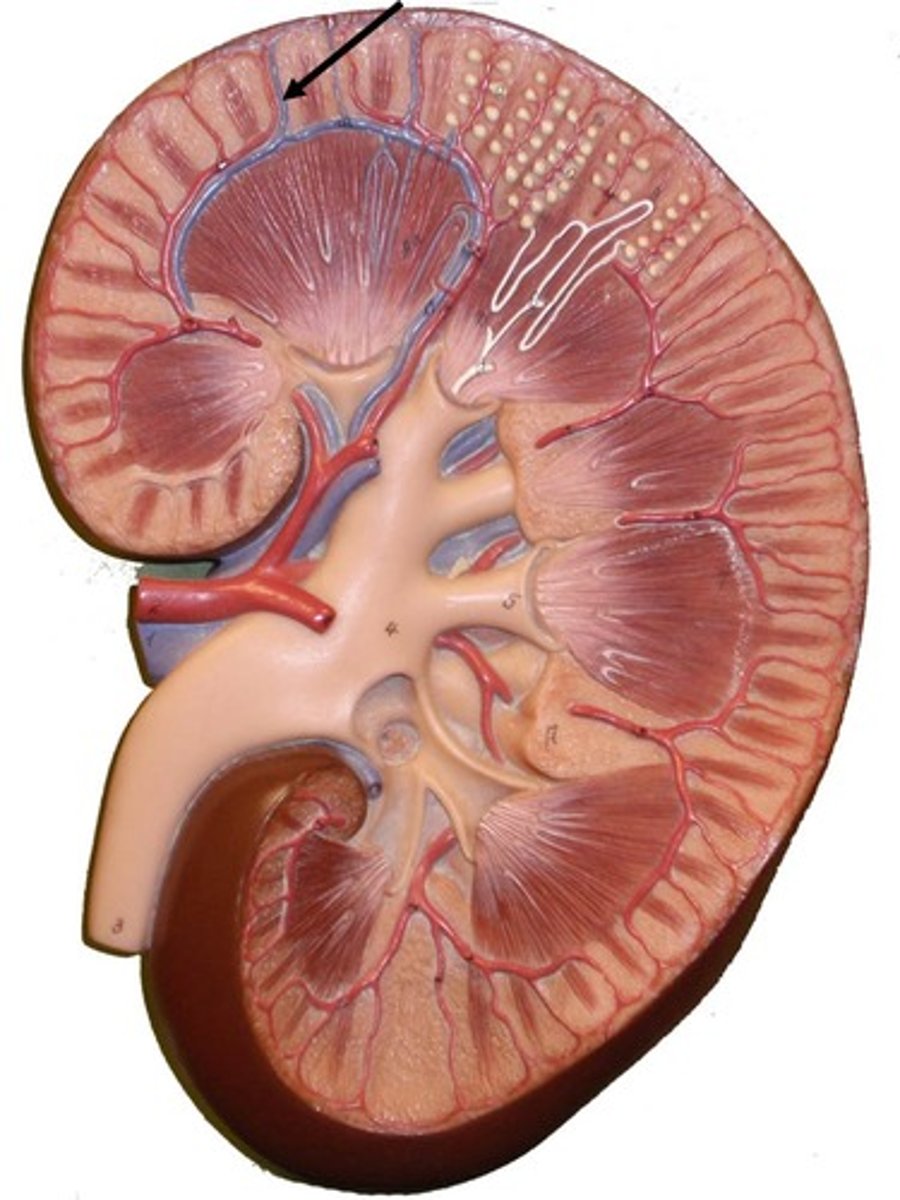

kidney

fibrous capsule

outer covering

renal cortex

renal medulla

renal papilla

major calyx

minor calyx

renal pelvis

renal pyramids

ureter

Pin in the middle

renal columns

renal artery

renal vein